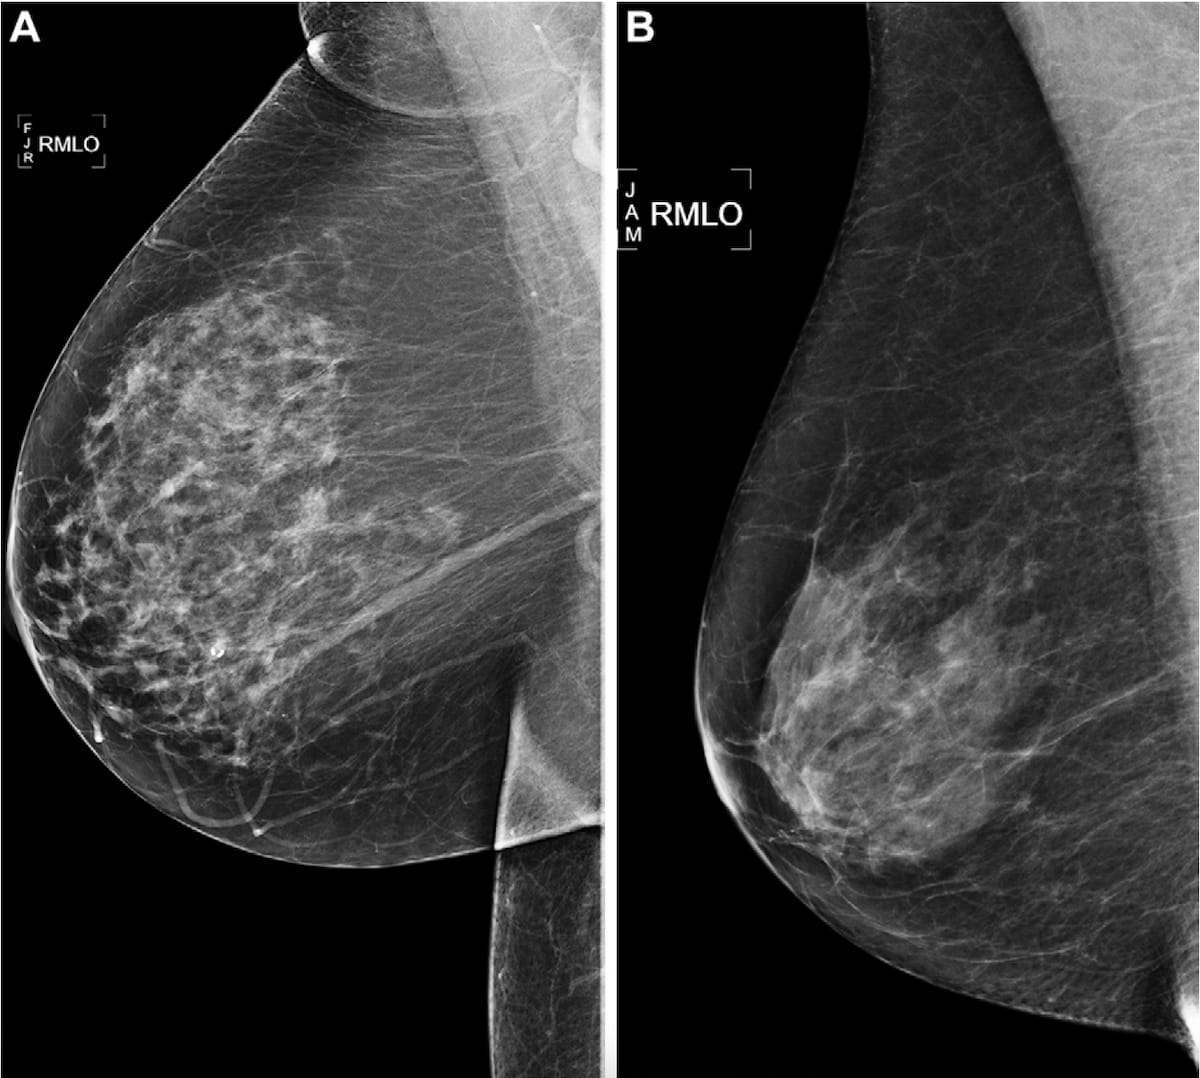

Here one can see proper medial lateral indirect screening mammograms. The left picture revealed a damaging mammogram discovering and a Mirai AI danger rating of higher than a 90 percentile danger in 2016 for a 73-year-old lady who developed breast most cancers in 2021. The second picture revealed a Mirai AI danger rating of lower than a ten percentile danger in 2016 for a 73-year-old lady who did develop breast most cancers throughout the five-year follow-up interval. (Images courtesy of Radiology.)